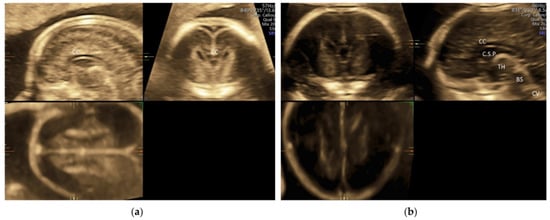

5.1. 3D Neurosonography